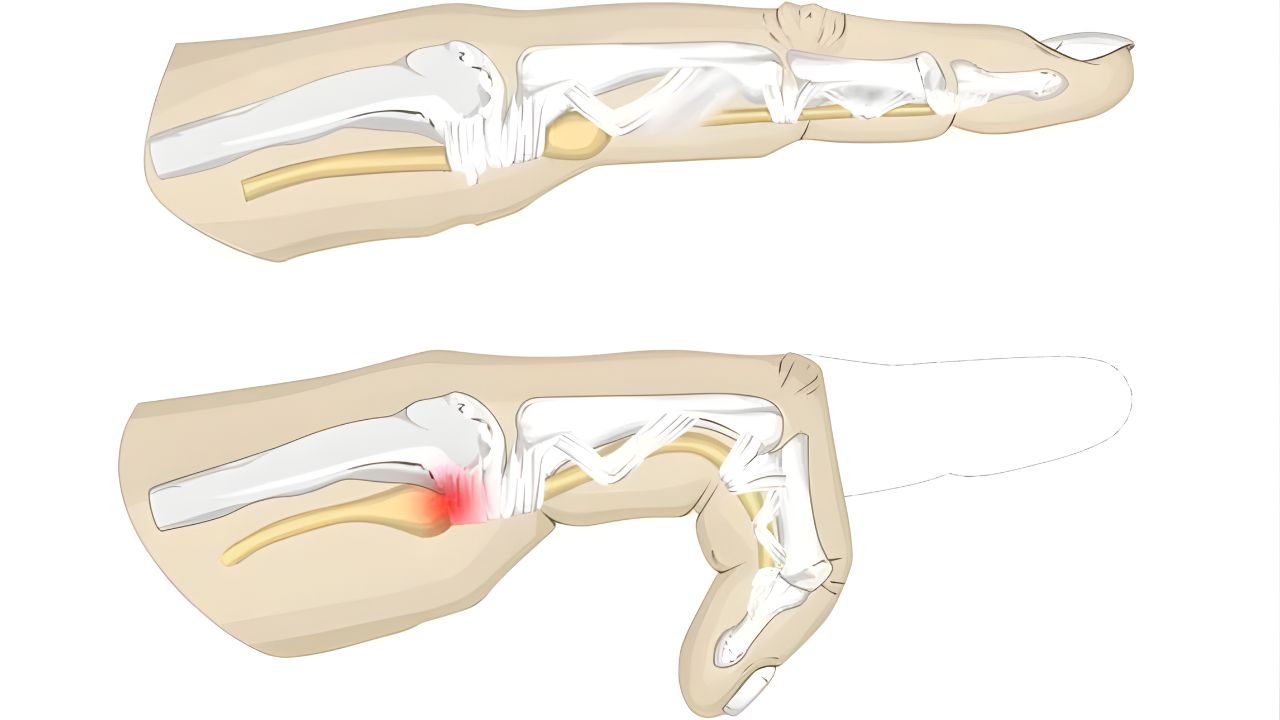

Agendar consulta O Dedo em Gatilho é uma condição dolorosa em que um dos dedos da mão trava em uma posição dobrada. Ao tentar esticá-lo,

Agendar consulta O Dedo em Gatilho é uma condição dolorosa em que um dos dedos da mão trava em uma posição dobrada. Ao tentar esticá-lo,